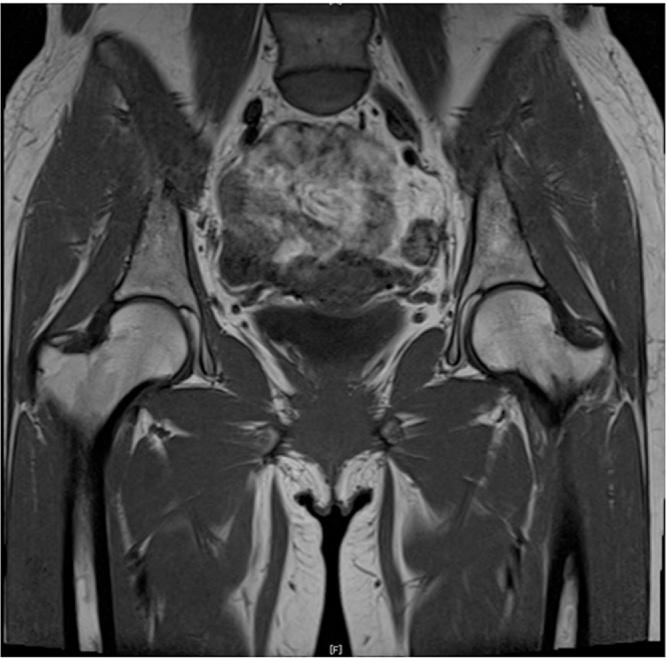

A 34-year-old female patient with rapid bilateral loss of vision was diagnosed Vogt-Koyanagi-Harada syndrome. She immediately received corticosteroid pulse therapy. While undergoing therapy, she complained of groin pain. The initial MRI of the hip did not show abnormal findings. As the right proximal thigh pain progressed, an MRI of the lumbar spine was performed. No compression of the spinal cord was observed, and right ONFH was suspected on the basis of a characteristic band image. The patient was diagnosed with Stage 1 ONFH 7 weeks after the initial symptoms. She was successfully treated by joint-preserving regenerative therapy using growth factor. After surgery, the patient completely recovered from pain.

一名34岁女性患者因双眼视力迅速丧失被诊断为Vogt-小柳原田综合征。她立即接受了皮质类固醇脉冲治疗。在治疗过程中,她主诉腹股沟疼痛。最初的髋关节MRI未显示异常。随着右大腿近端疼痛加剧,进行了腰椎MRI检查。未观察到脊髓受压,根据特征性带状影像怀疑为右股骨头坏死。在出现初始症状7周后,该患者被诊断为1期股骨头坏死。通过使用生长因子的保关节再生疗法,她得到了成功治疗。术后,患者疼痛完全缓解。